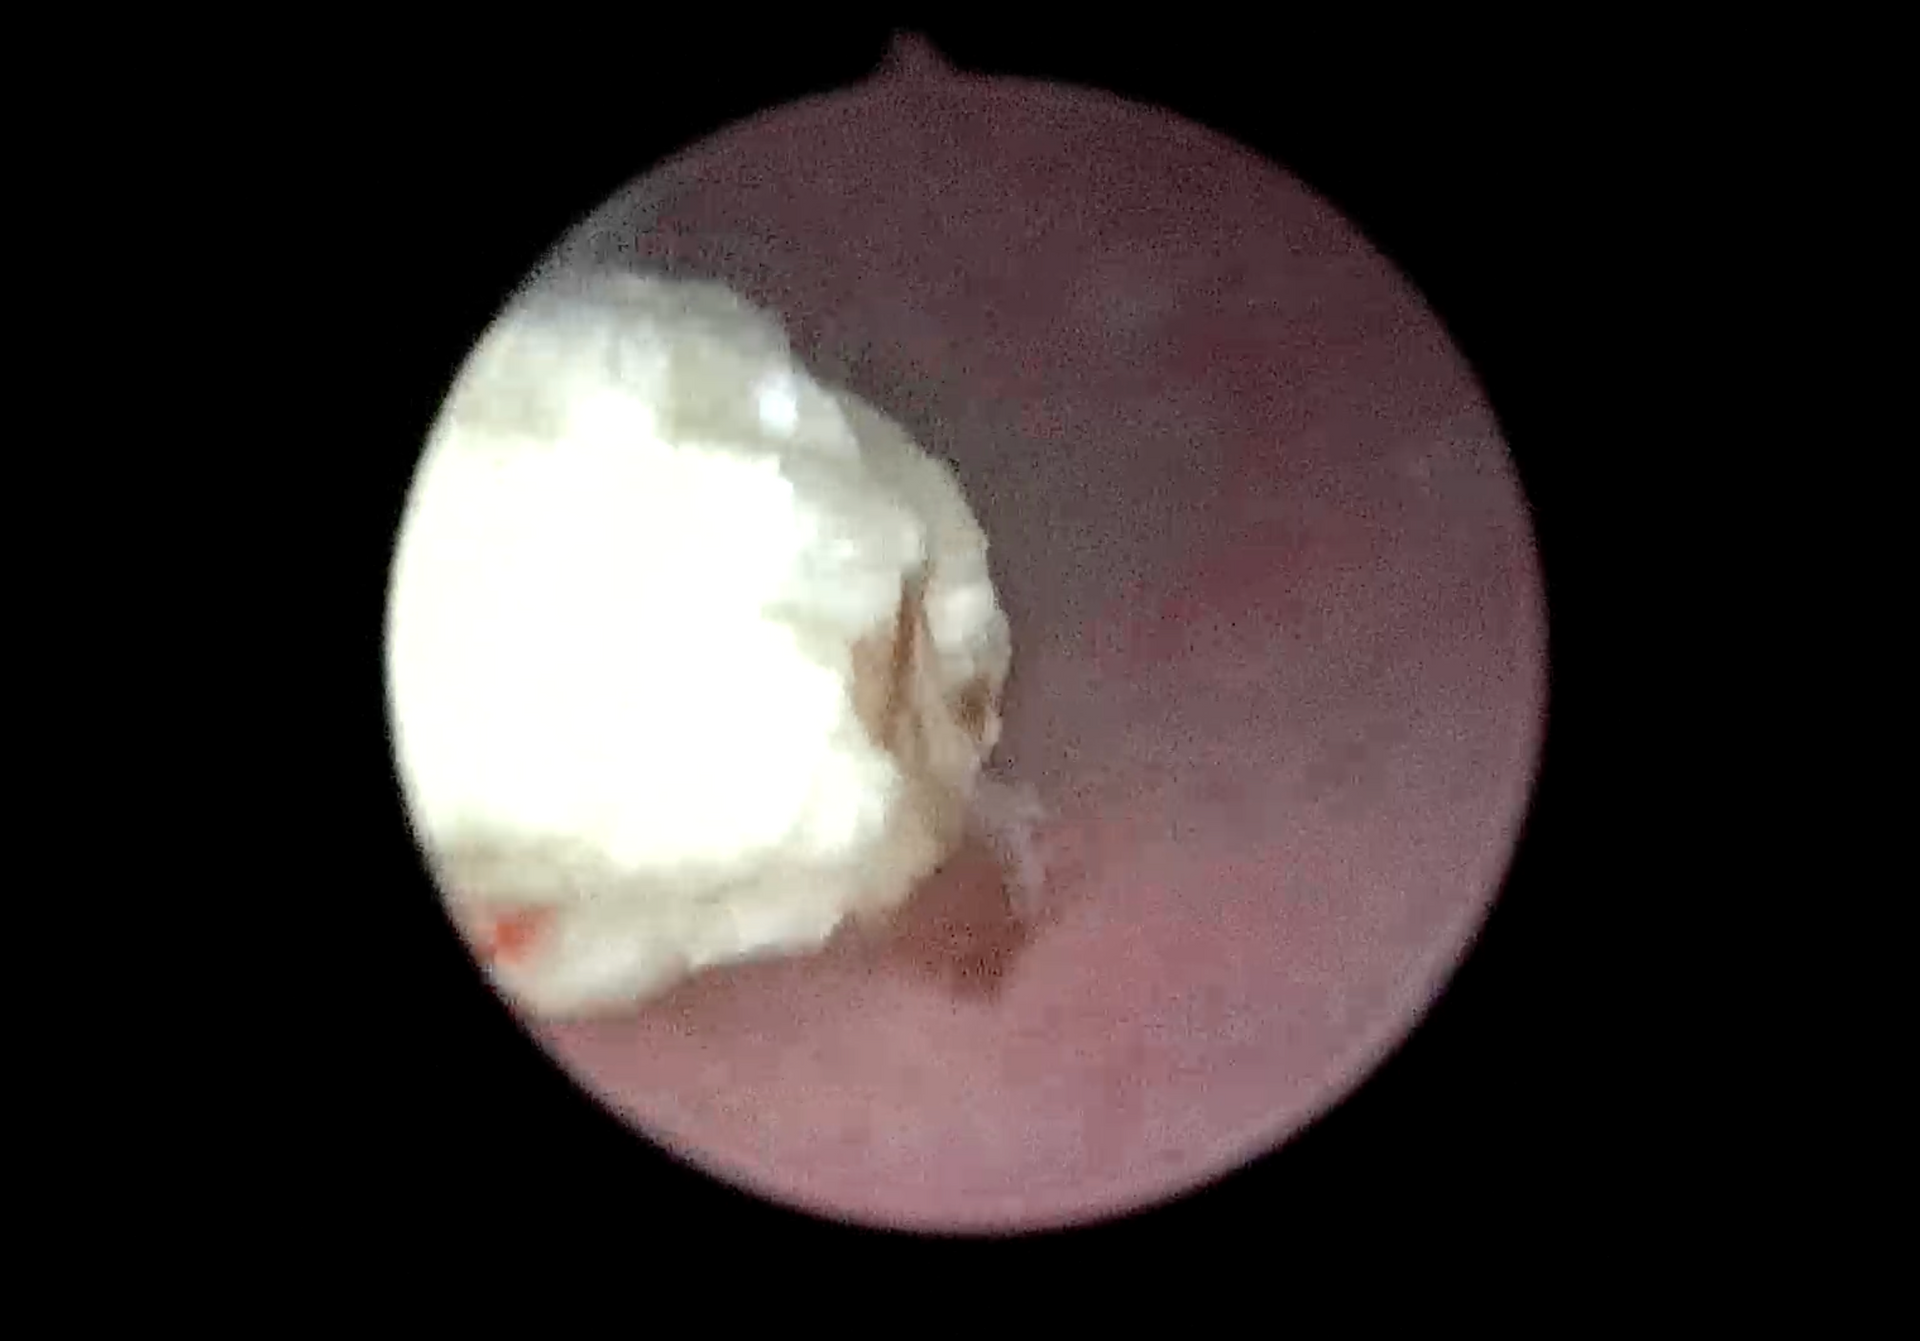

- Rhinoscopie → exploration des cavités nasales (écoulements, éternuements chroniques, saignements)

- Gastroscopie → exploration de l’estomac et de l’œsophage (vomissements chroniques, ingestion de corps étranger)

L’endoscopie permet aussi, dans certains cas, de retirer des corps étrangers (morceau d’os, épillet, jouet, etc.) sans chirurgie ouverte.